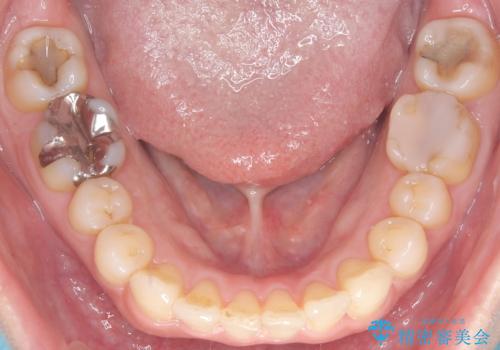

治療中は咬合バランスや歯列の中心(正中)の位置にも注意を払い、最終的には上下の正中が一致し、左右の臼歯関係も理想的な形に改善されました。見た目の変化はもちろん、かみ合わせの安定や清掃のしやすさも向上。

患者さんからは「笑ったときの印象が大きく変わって嬉しい」「しっかり噛めるようになった」との感想をいただきました。現在は保定装置で後戻りを防ぎながら、良好な状態を維持しています。